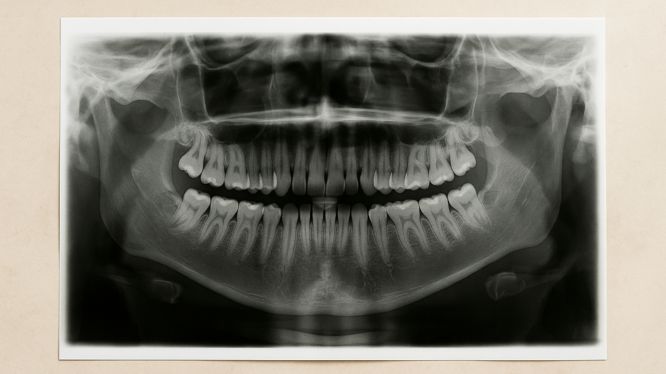

🖼️ 1. Radiografía Panorámica (Ortopantomografía)

¿Qué es?

Una imagen extraoral que muestra en una sola toma todos los dientes superiores e inferiores, desde las raíces hasta la articulación temporomandibular (ATM).

¿Para qué sirve?

- Ver si hay muelas del juicio, dientes retenidos o ausentes

- Evaluar el estado general del hueso alveolar

- Detectar lesiones, quistes o infecciones

- Confirmar si hay alguna anormalidad en la erupción dental

¿Cómo se realiza?

El paciente se coloca de pie frente a la máquina, apoyando la cabeza y mordiendo una pequeña guía. Además, la máquina gira alrededor de la cabeza durante unos segundos.

🕒 Duración: menos de 2 minutos

💡 No requiere preparación previa

📌 Es indoloro y rápido